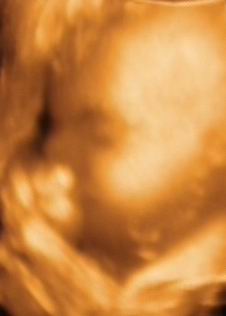

megvolt ma a 4D. Hát a mi kis madarunk elég kis szégyenlős fajta, ismét a lábaival takarta magát, nagyon nehezen tudtunk az arcocskájához férni, de azért sikerült egy-két képet csinálni. Holnap bescannelem, aztán felteszem. Olyan édes volt

Mindenesetre így is látszott a lényeg, hogy fejjel lefelé van, de elég furcsa pozícióban.

A feje van jobbra lent, majdnem középen, aztán a köldökemnél van a háta-hasa-feneke, majd a lába visszafordul a teste elé, egészen le a fejecskéjéig. Szóval olyan kis kifli formában helyezkedik el. Elég érdekes, enyhén jóga-pozitúra

Egyébként 1046 gr, szép nagyot nőtt, a fejecskéje 25.7 cm. Az UH alapján a kora is stimmel, 2 nappal látták idősebbnek.